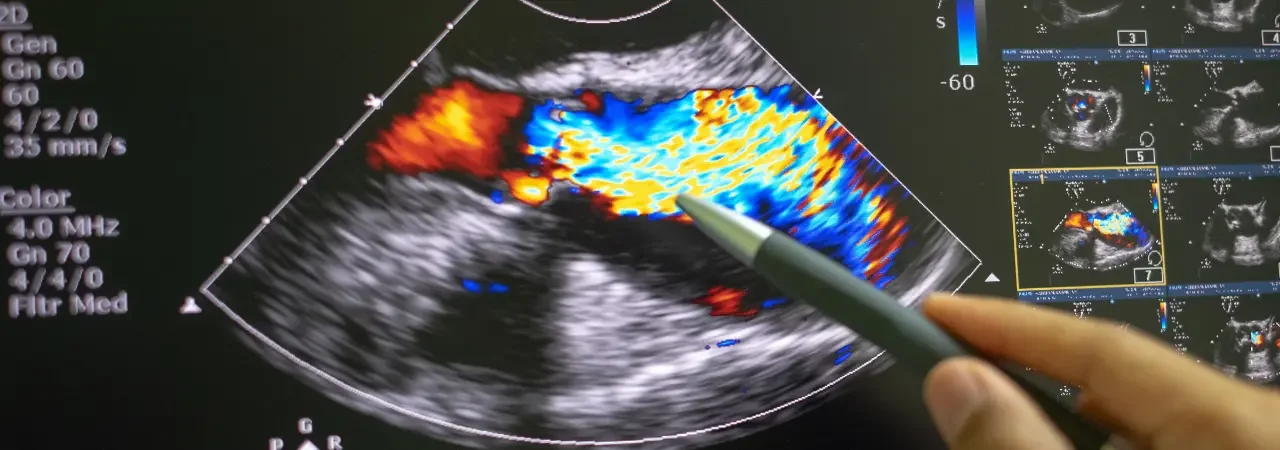

Kan kültürleri, TTE/TEE ve BT-PET ile kapsamlı değerlendirme

Önce çoklu set kan kültürü alır, ardından TTE ile başlar, TEE ile ve gerekirse BT-PET ile vejetasyon, abse, fistül ve protez gevşemesini doğrularız. Böylelikle, emboli riski yüksek vejetasyonları, iletim bozukluğu yapan abseleri ve gizli odakları görünür kılar, karar ağacını hızla çalıştırırız. Ayrıca, böbrek fonksiyonu, beslenme durumu ve antimikrobiyal duyarlılık verilerini eşleştiririz.